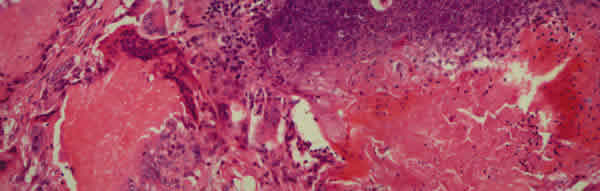

Fig. 3. Nidos de células basófilas "células fantasmas", y reacción inflamatoria con numerosas células gigantes tipo cuerpo extraño.

Se trata de masas sólidas, encapsuladas, con células basófilas y fantasmas (6,13), coincidiendo con el caso expuesto (fig. 3). Esto, unido a la localización cutánea es suficiente para su diagnóstico (13). El estroma suele contener calcificación [según autores, entre un 50% (1) a un 98% (5) de ellos], osificación y células inflamatorias. Las células gigante tipo cuerpo extraño, y células escamosas nucleadas son menos específicas, pero ayudan al diagnóstico (13). Aunque raro, la dermis puede sufrir cambios atróficos, con disminución del colágeno, fragmentado, e incluso tejido elástico ausente, pudiendo apreciarse incluso áreas similares a queloides o cicatrices hipertróficas (14).